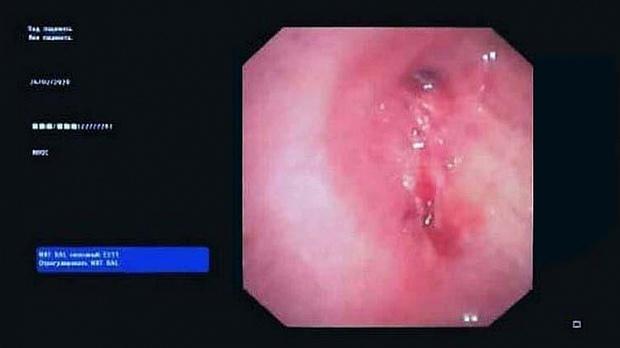

Вчера в отделении эндоскопии успешно апробировано окклюзия бронхоплеврального свища.

Пациент К. 1960 г.р., после правосторонней пульмонэктомии от 2019 г. поступил в отделение многоплановой хирургии. При плановой бронхоскопии выявлена несостоятельность культи правого главного бронха, устье свища до 0.3 см, откуда поступает слизисто-гнойное содержимое. В устье свища определяется сшивающая скоба. Также у пациента имеется дренажная трубка справа в 7 межреберье, подключаемая к активному отсосу.

Во время повторной бронхоскопии под интубационным наркозом установлен окклюдер из ИМН другого назначения (PULL THRU) в устье свища. Поперечные резиновые лепестки на окклюдере и скоба в устье свища должны надёжно фиксировать положение окклюдера.

Оборудование: видеобронхоскоп Olympus 180, окклюдер PULL THRU( Medivators)